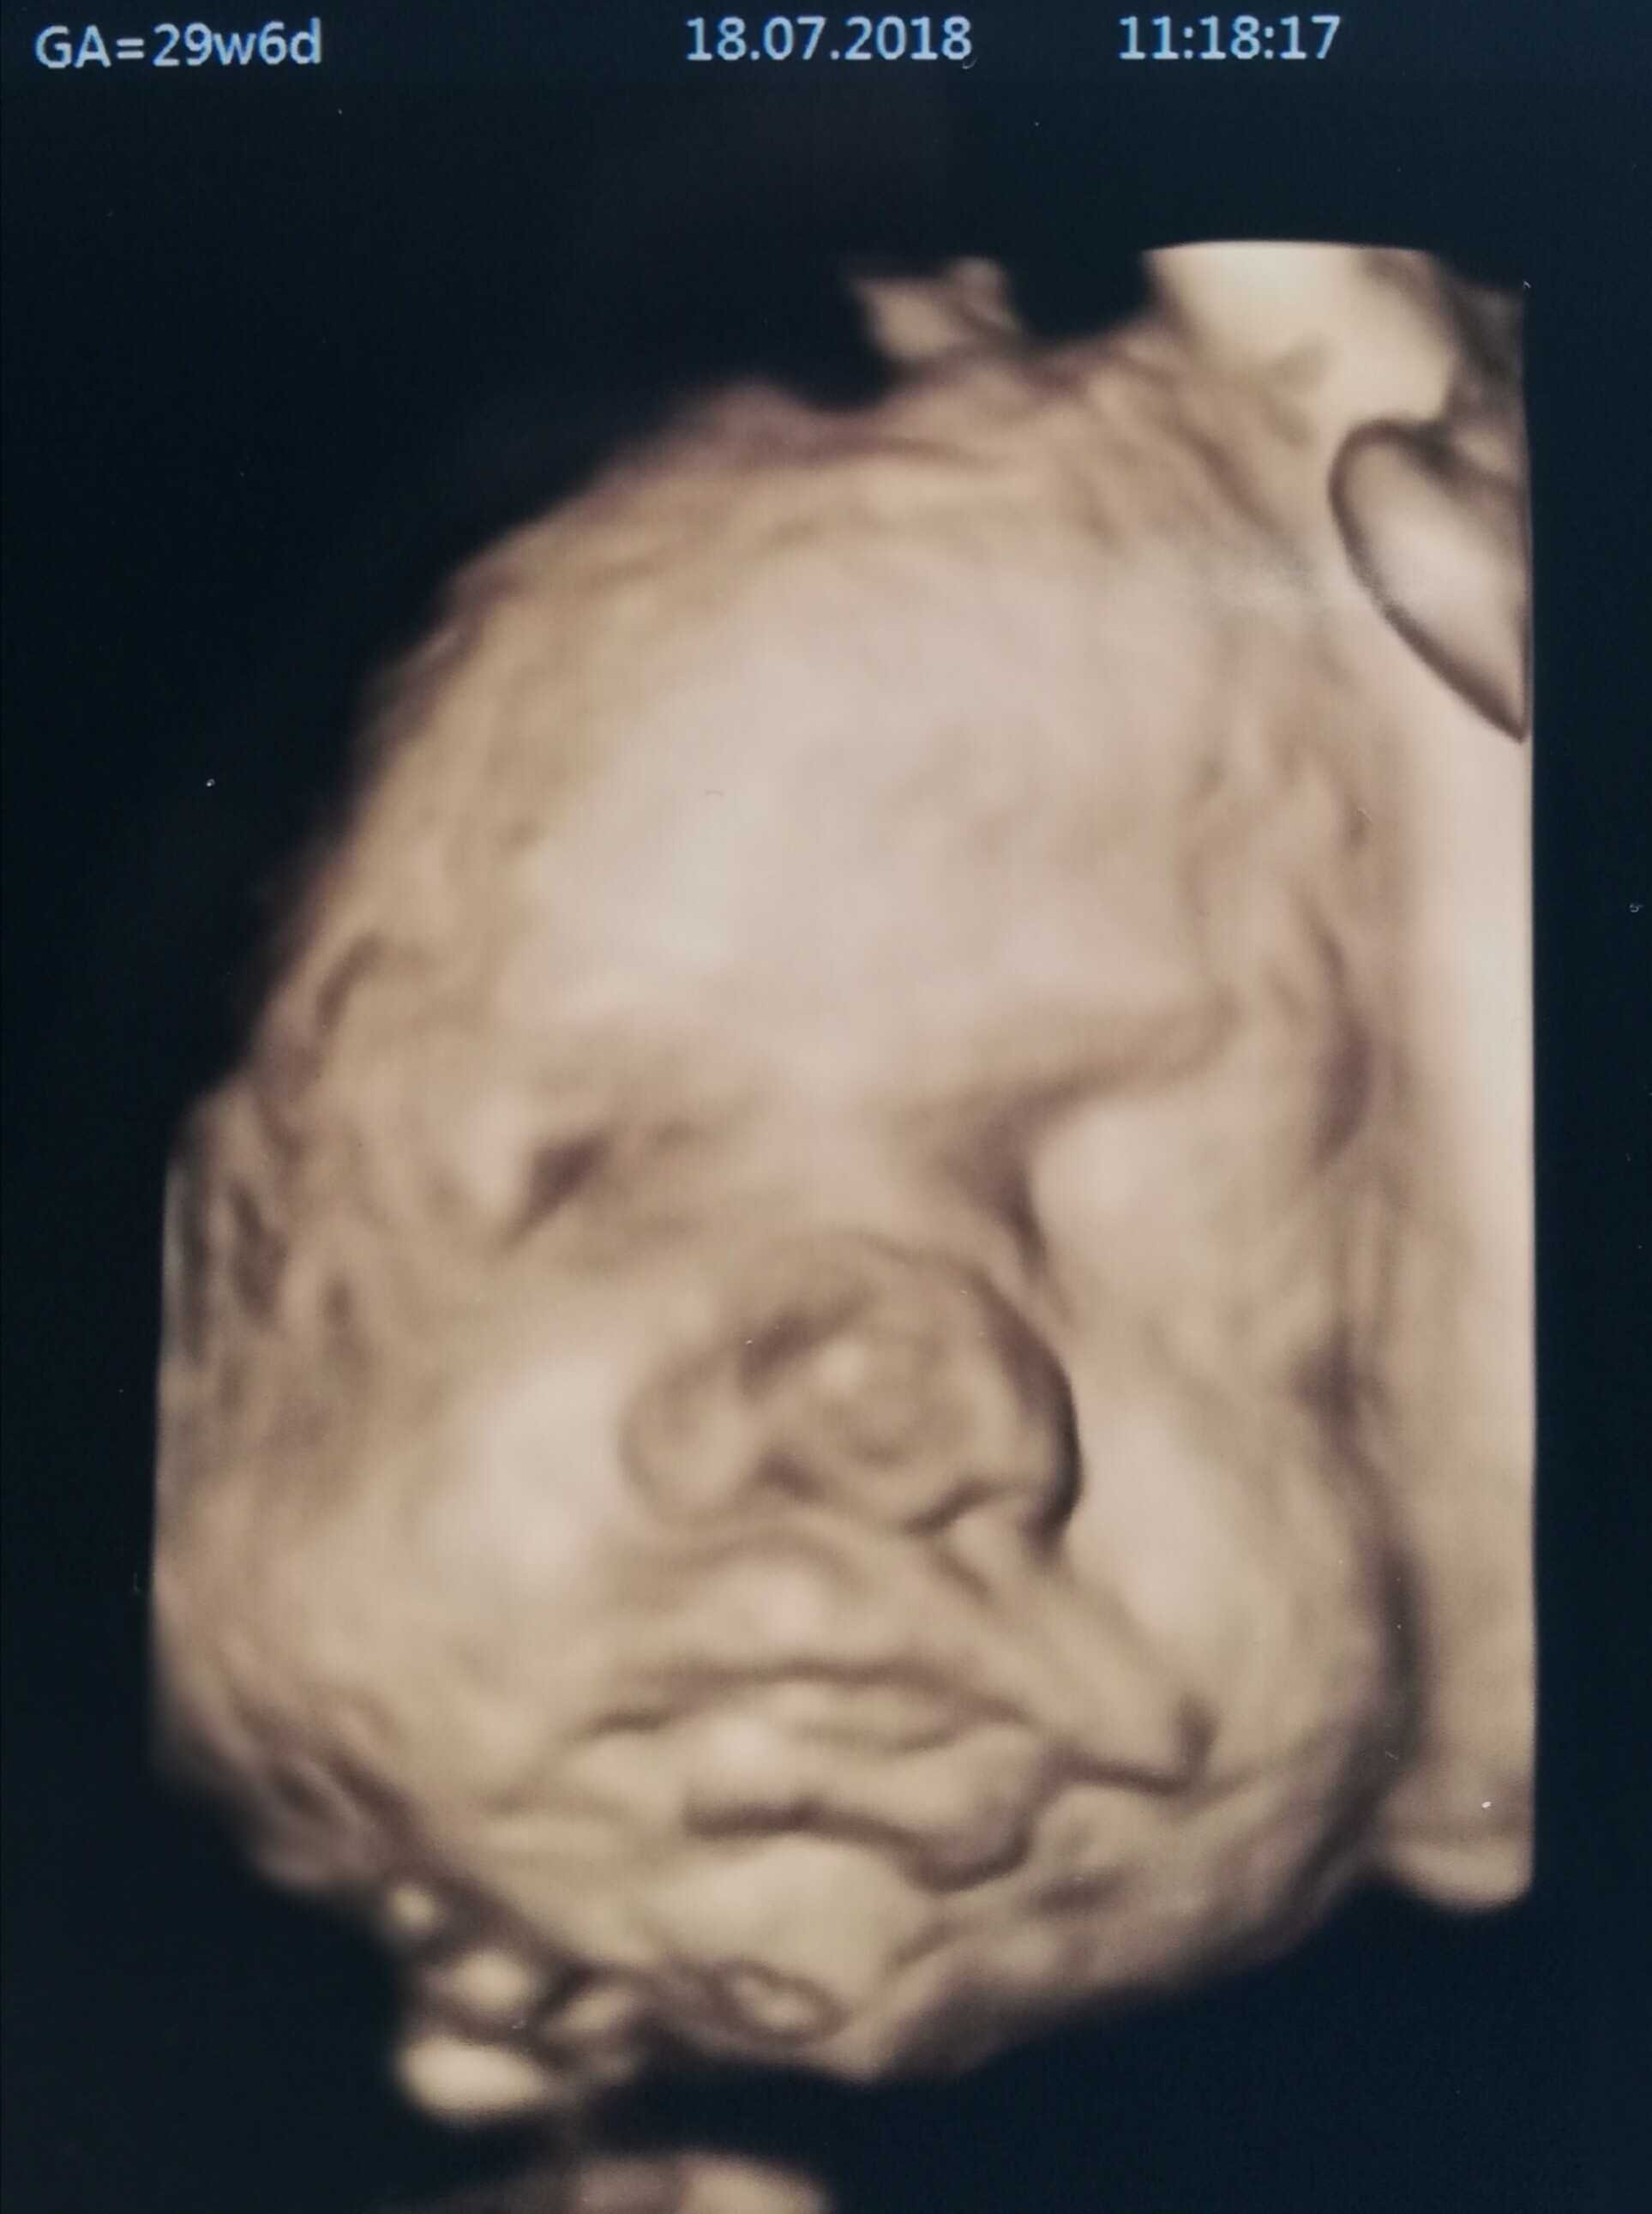

U mnie 27,2 tc. Ruchy czuje wyraźnie mocniej mimo łożyska na ścianie przedniej.Dzis mam wizyte zwykłą. Zrezygnowałam z usług Pani profesor i bardzo powoli zaczynam odstawiać niektóre leki. Z najważniejszych to odstawiłam metforminę (po uzgodnieniu z diabetologiem). I Duphaston zmniejszyłam do 0,5 x2 a jak mi sie skończy to juz nie kupie. Za to luteinę biorę pod język co 6 godzin. Trzecie usg mam 24.07 bede 28,1 tc (wczesnie ale moja lekarka mowila ze wysle mnie jeszcze w 32 i 36 tc ze względu na moje problemy autoimmunologiczne). Na koniec miesiąca mam wizyte u proktologa, ktory ma mi dac zaświadczenie o cc (przy poprzednim porodzie miałam pękniecie III krocza i odbytu przy wadze dziecka 2900g) - ale jeszcze nie podjęłam decyzji czy napewno pojde na cc.